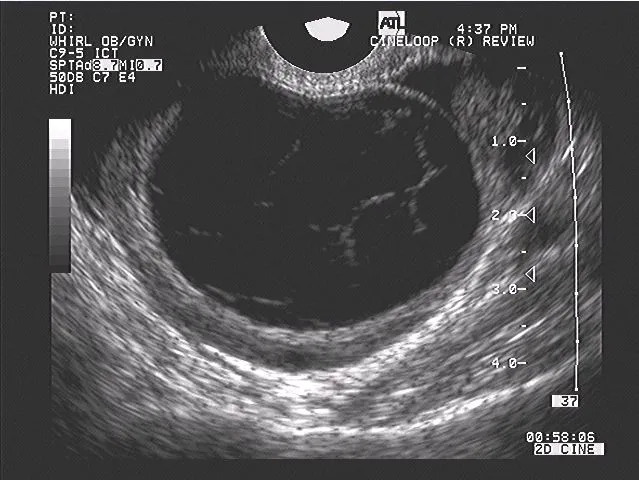

The corpus luteum develops the richest blood supply per gram of any tissue, with capillary density reaching 2,000 vessels/mm³. This vascularization enables massive steroid production but also creates vulnerability to ischemic regression. Vascular endothelial growth factor (VEGF) expression increases 50-fold during luteinization, promoting angiogenesis essential for progesterone synthesis.

| Luteal Phase Day | Progesterone (ng/mL) | Estradiol (pg/mL) | LH (mIU/mL) | Key Events | Clinical Significance |

|---|---|---|---|---|---|

| 1-3 | 1-5 | 100-200 | 5-15 | Early luteinization | Implantation window opens |

| 4-6 | 5-15 | 150-250 | 2-8 | Peak angiogenesis | Endometrial receptivity |

| 7-9 | 15-25 | 200-300 | 1-5 | Maximum function | hCG rescue window |

| 10-12 | 10-20 | 150-250 | 1-5 | Functional plateau | Pregnancy detection |

| 13-14 | 2-5 | 75-150 | 2-10 | Luteolysis begins | Menstruation trigger |

Steroidogenic Luteal Machinery

Luteal Regression Mechanisms

💡 Master This: Human chorionic gonadotropin (hCG) rescues the corpus luteum by mimicking LH action, maintaining progesterone production above 20 ng/mL through the first 8-10 weeks of pregnancy. Without hCG rescue by day 11-12 post-ovulation, prostaglandin F2α triggers irreversible luteolysis within 48 hours.